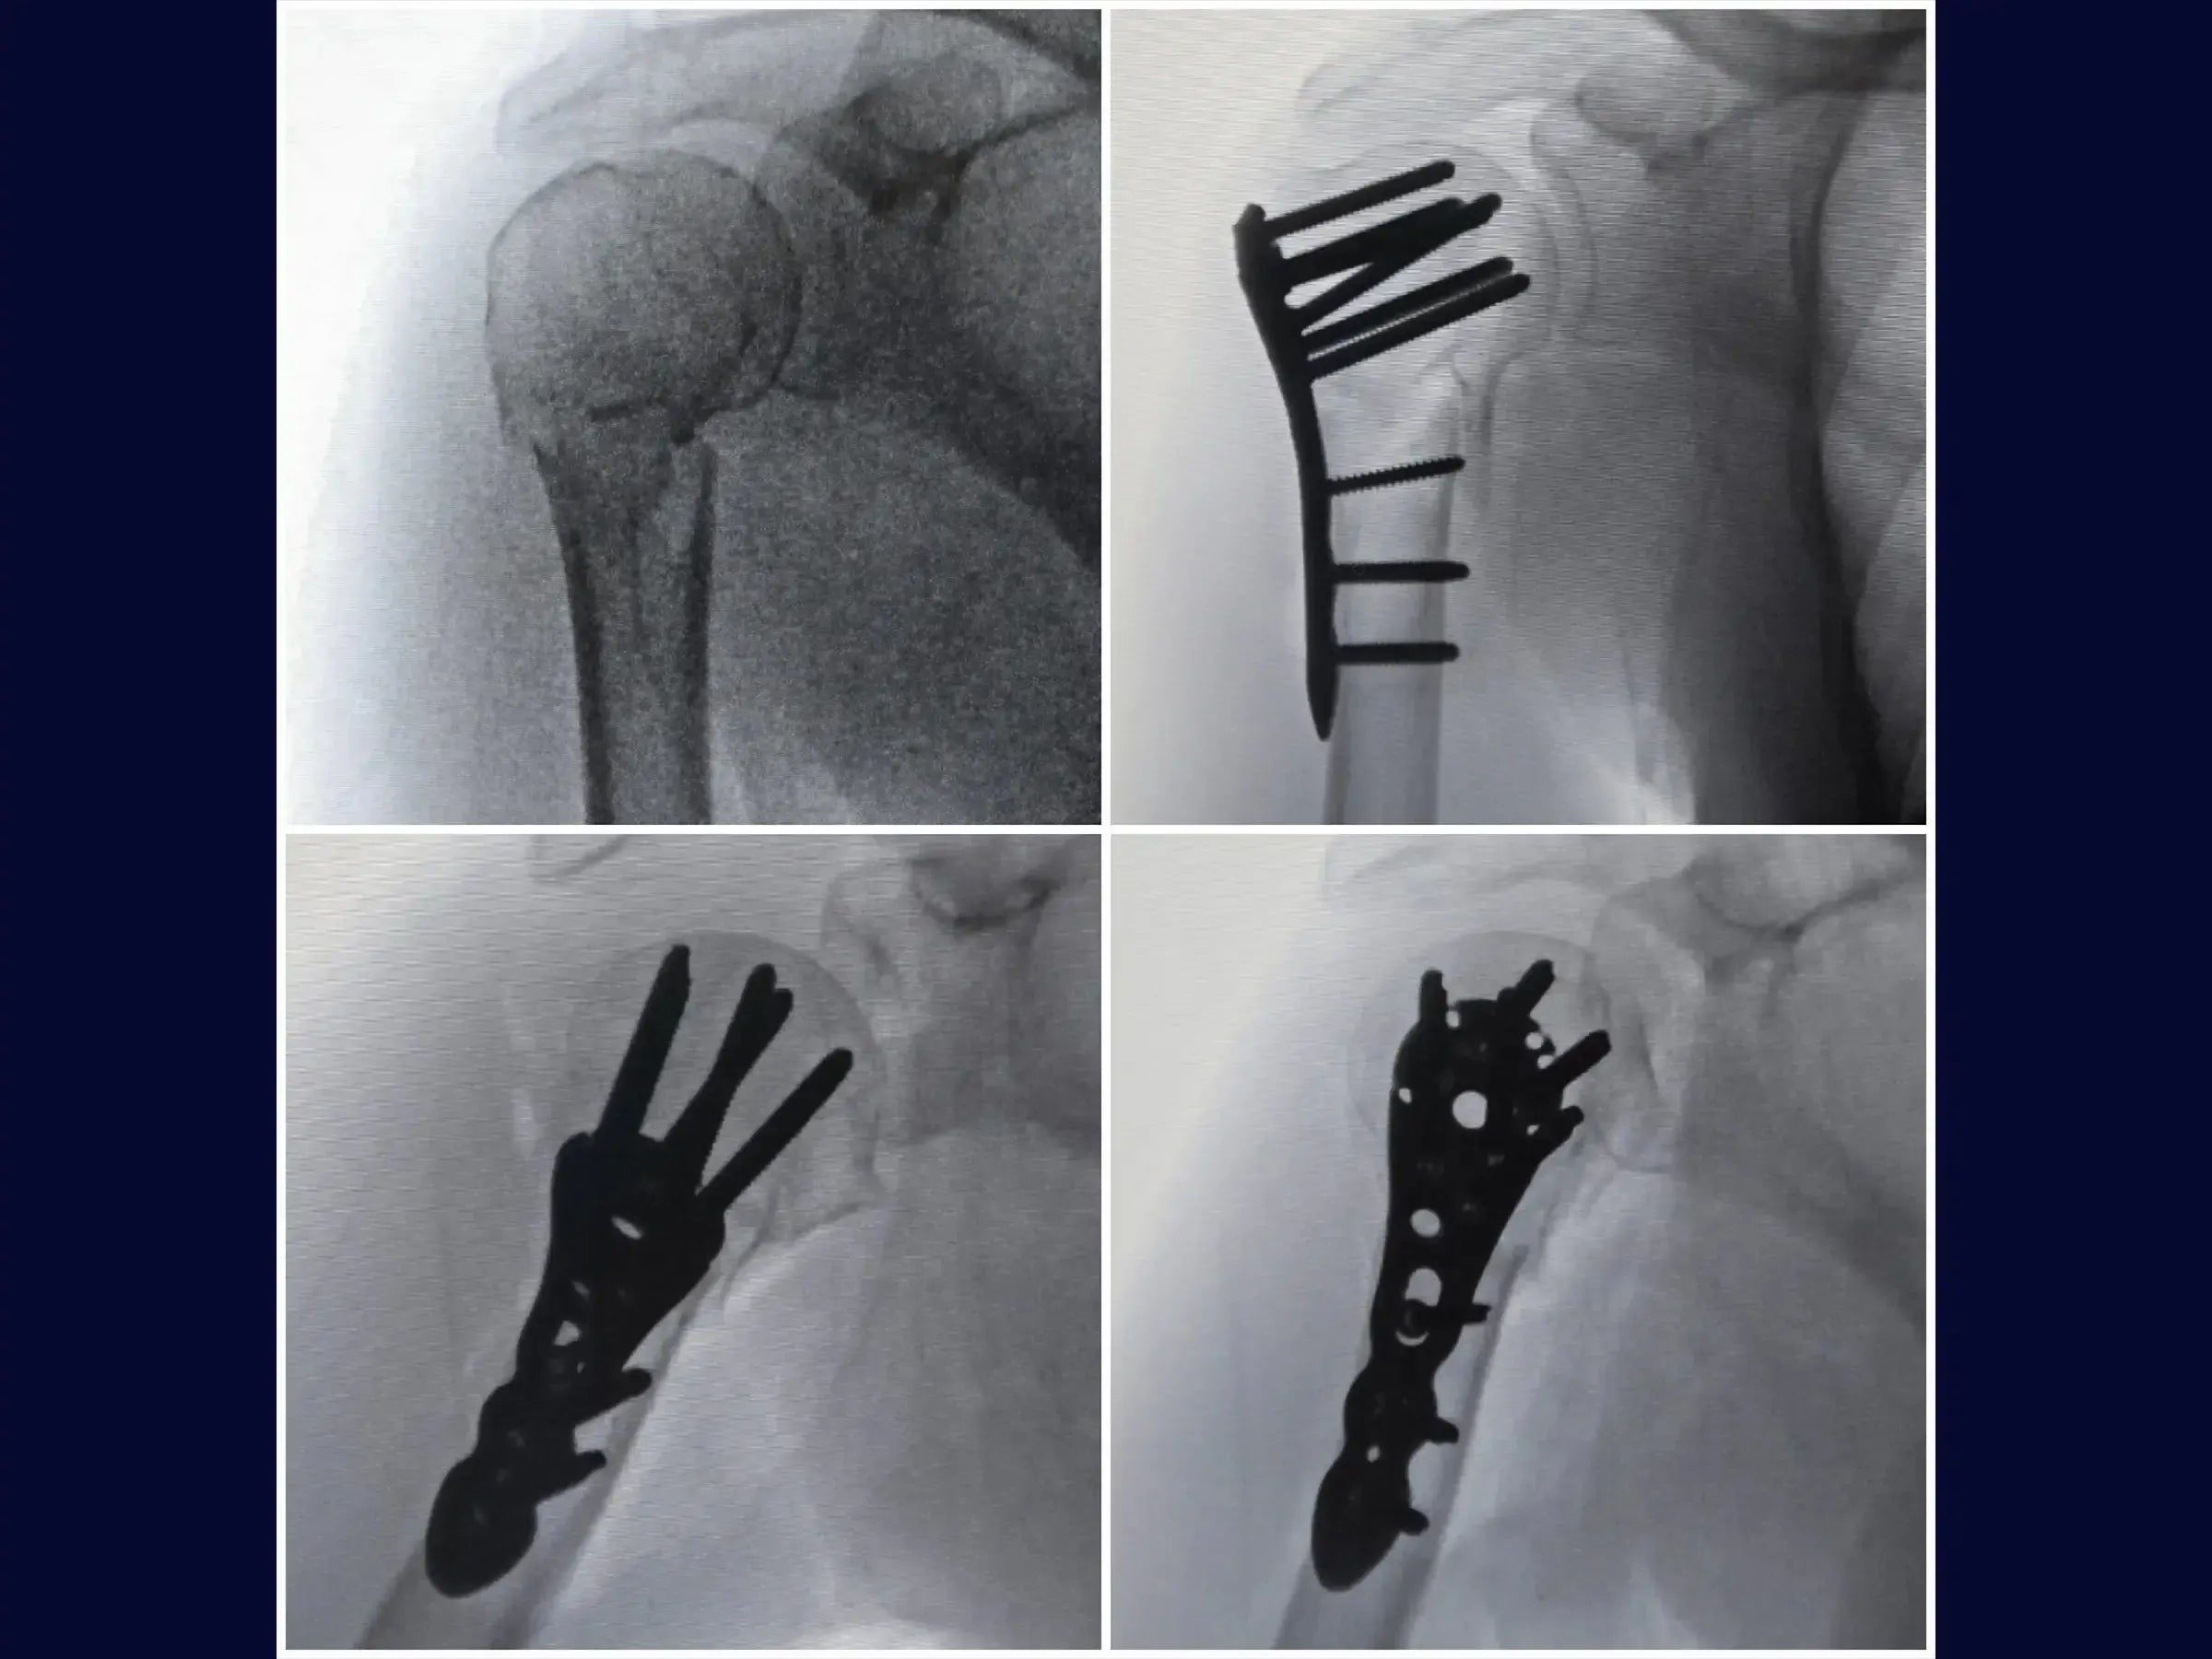

- Anatomical reduction of proximal humerus fractures and provisional fixation.

- Manoeuvres for valgization of the humeral head.

- Brocage technique and measurement of screws for definitive subchondral fixation.

- Correction of Varus: Specific maneuvers (abduction, traction with high-resistance wire, thumb pressure, and inverted condylar grip) for valgization of the humeral head.

- Secure Subchondral Fixation: Drilling methodology with sensitivity for precise positioning of screws in the subchondral bone, without perforating the cartilage, with initial insertion of the screws from the calcaneus.

- Post-Operative Stability: Demonstration of the rotator cuff repair to the plate for additional stabilization, especially in osteoporotic bones, and management of the long head of the biceps.